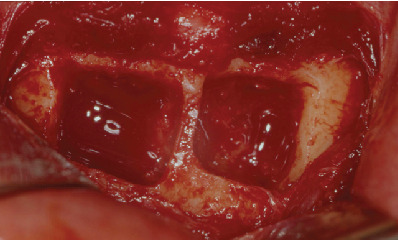

Figure 5.

Bone block stabilization by screws.

Figure 6.

Coverage of the surgical site with deproteinized bovine bone (Bio-Oss®, Geistlich Biomaterials, Wolhusen, Switzerland).